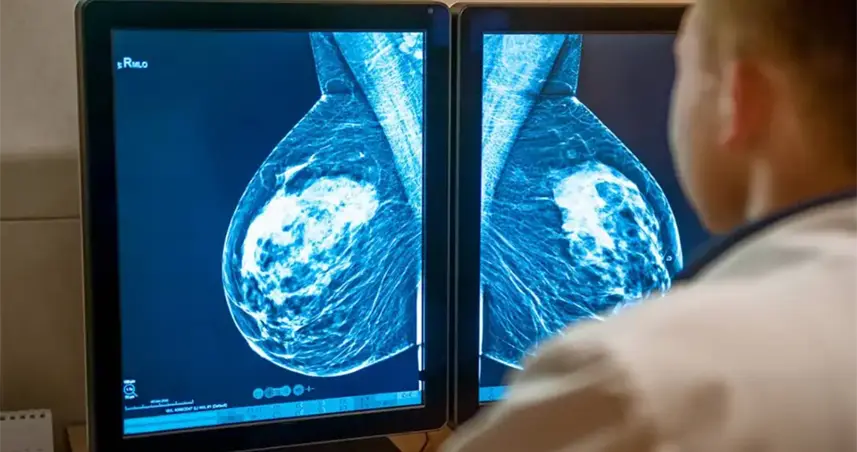

Sídney (Australia).- Un sistema de inteligencia artificial (IA) desarrollado en Australia podría transformar la forma en que se detecta y se previene el cáncer de mama, al identificar a mujeres con alto riesgo de desarrollar la enfermedad tras recibir una mamografía aparentemente normal, según un estudio publicado este miércoles.

La investigación, difundida en la revista The Lancet Digital Health, analiza una herramienta denominada BRAIx, que utiliza algoritmos de aprendizaje profundo para examinar imágenes mamográficas.

El sistema calcula una puntuación individual de riesgo de cáncer de mama en los años posteriores al examen, lo que permite anticipar posibles diagnósticos futuros.

El estudio, realizado por la Universidad de Melbourne, se basó en datos de más de 96.000 mujeres que participaron en el programa público BreastScreen en el estado de Victoria, al sur de Australia.

A partir de las mamografías, los investigadores calcularon el llamado índice de riesgo BRAIx.

Esta puntuación estima la probabilidad de desarrollar cáncer en el momento del cribado o en los cuatro años siguientes.

Los resultados mostraron que el sistema predice con gran precisión qué mujeres tienen mayor probabilidad de desarrollar la enfermedad tras un resultado negativo.

En particular, el 2 % de las mujeres con el índice de riesgo más alto presentaba cerca de un 9,7 % de probabilidad de recibir un diagnóstico de cáncer de mama en los cuatro años posteriores.

Esa cifra resulta comparable o incluso superior al riesgo de algunas portadoras de mutaciones genéticas asociadas a la enfermedad.